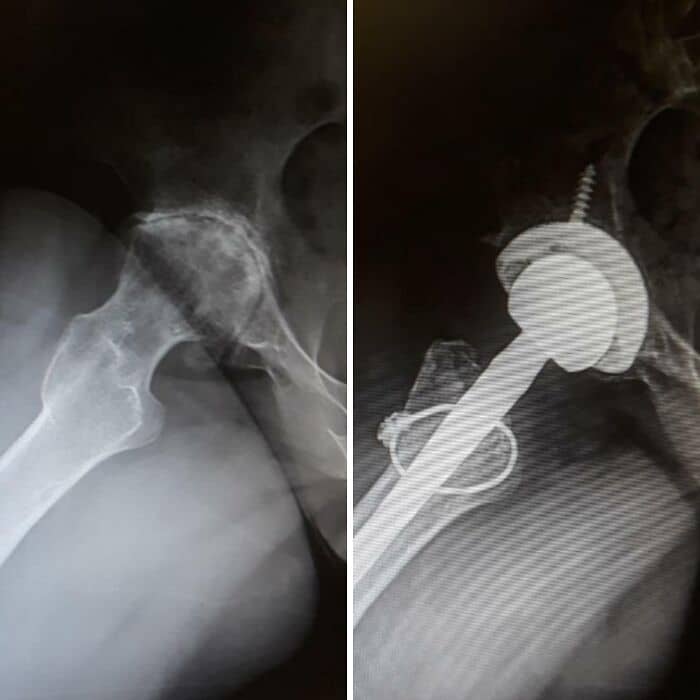

#46 Before And After Hip Replacement Surgery